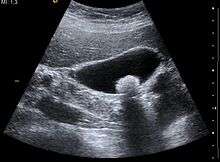

Imaging

Ultrasound is often the first imaging examination performed when galbladder disease is suspected. Other imaging options include MRCP (magnetic resonance cholangiopancreatography), ERCP and percutaneous or intraoperative cholangiography. A cholescintigraphy scan is a nuclear imaging procedure used to assess the condition of the gallbladder.